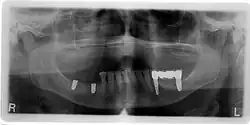

-

OPT mit Zahnlücke Regio 26 und Kugellmessaufnahme mit Kugeldurchmesser 5 mm -

Zahnlücke / Schaltlücke Regio 26 (Seitenansicht) -

Zahnlücke / Schaltlücke Regio 26 (Aufsicht) -

Röntgenbild eines Zahnimplantates in Regio 26 unmittelbar nach internem Sinuslift -

Freigelegtes Zahnimplantat Regio 26 -

Verschraubte Implantatkrone mittels CEREC hergestellt -

Eingesetzte verschraubte Implantatkrone in Regio 26 (Seitenansicht) -

Eingesetzte verschraubte Implantatkrone in Regio 26 (Aufsicht)